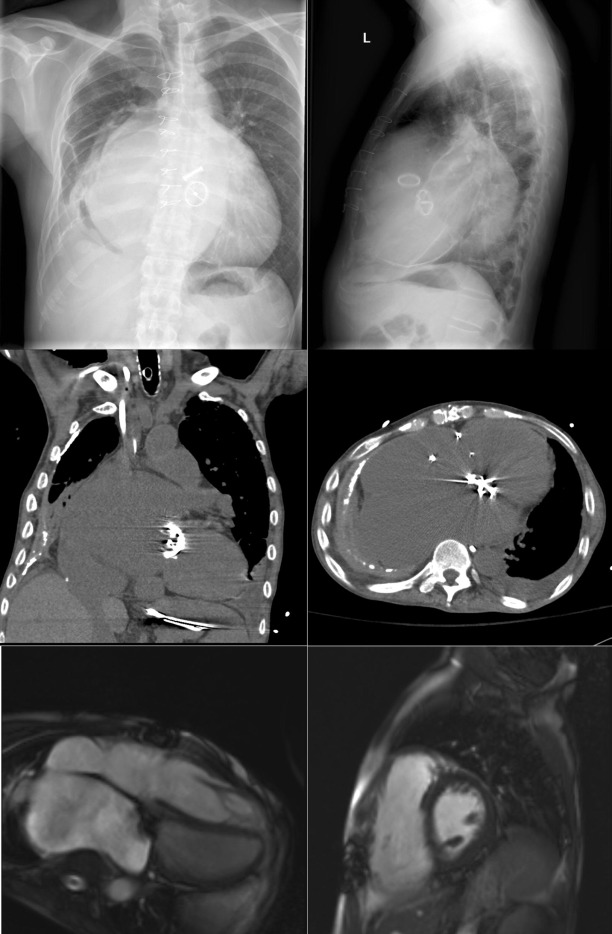

Pericardial Calcification

Pericardial calcification ( Figs. 27-1 to 27-4 ) is most prominent in the interventricular and atrioventricular grooves, and lateral to the right atrial and ventricular walls ( Graphic 27-1 ). When looking for pericardial calcification, it is necessary to scrutinize the lateral chest radiograph well, particularly the diaphragmatic surface. Pericardial calcification does not usually involve the left heart as much the right heart, and it does not often involve the apex (which, if calcified, is far more often due to prior infarction). Pericardial calcification should prompt serious consideration of the diagnosis of constrictive pericarditis, and clinicians should seek other radiographic and clinical features of constriction.

Myocardial Calcification ( Figs. 27-5 to 27-9 )

A calcified ventricular aneurysm is seen as a fine dense line when viewed on edge and is consistent with an old transmural infarction. On the frontal chest radiograph, an anterolateral, or apical, calcified aneurysm may be visible. Rarely, a calcified septal aneurysm may be seen on a lateral chest radiograph. Myocardium may calcify following traumatic injury as well as postinfarction.